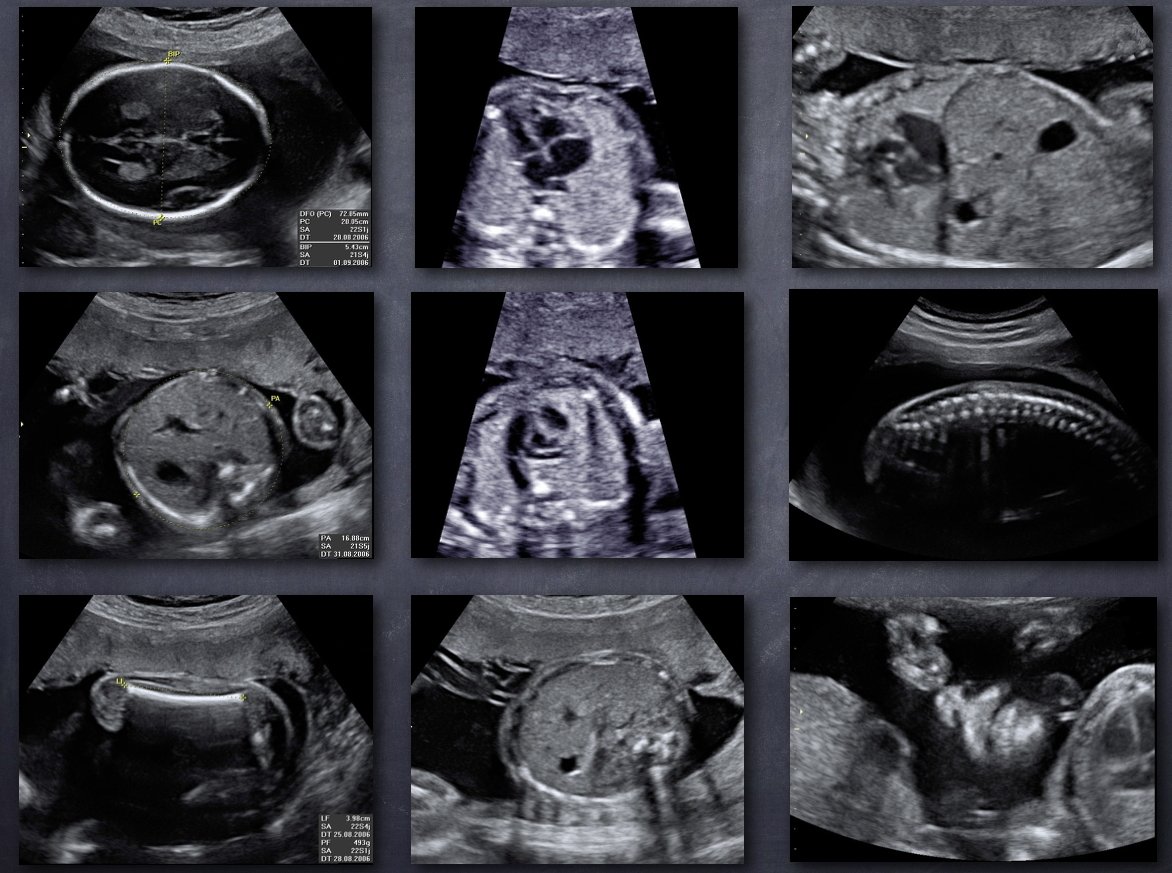

L'échographie au cours de la grossesse

Pour réaliser cet examen, un capteur émetteur-récepteur (sonde) est glissé sur la peau de votre ventre après application d’un gel destiné à favoriser le passage des ultrasons.

Dans certaines circonstances, il est intéressant d’utiliser un capteur adapté que l’on positionne dans le vagin afin d’être plus proche des structures étudiées. Dans ce dernier cas, le capteur est recouvert par une protection à usage unique. Cela n’est pas douloureux et reste sans danger pour la grossesse.

L’examen au cours de la grossesse comporte quatre parties dont l’importance varie selon le terme :

• Appréciation de la vitalité (activité cardiaque, mouvements fœtaux, éventuellement Doppler),

• Étude biométrique par la mesure de certaines parties déterminées afin de préciser la date de début de grossesse (1er trimestre) et de surveiller la croissance (2e et 3e trimestre),

• Analyse morphologique par l’observation de certaines structures fœtales (organes ou parties d’organe) définies, connues pour leur utilité dans le dépistage de pathologies fréquentes et/ou sévères

• Observation de l’environnement du fœtus (liquide amniotique, placenta, circulation sanguine….).